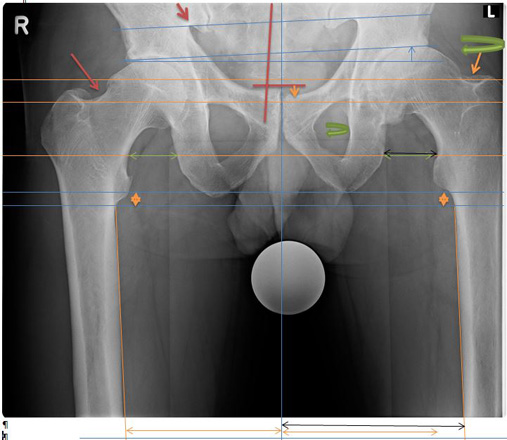

Becken Bild 1

Anhand der Original Aufnahmen werden Spannungsbedingte Ausweichhaltungen auf den folgenden Seiten sichtbar gemacht.

6848180

1.1

Aufnahme zeigt eine Verdrehung der linken Seite, anhand der Beckenlöcher.

Zudem muss das Becken seitlich verschoben sein.

Sichtbar anhand der Beinstellungen und der Verdrehung des Schenkelhalses.

Weiter wird ersichtlich, dass links das Becken hochgedrückt wird.

Eindeutig am Beckenspalt zu erkennen, das der Oberkörper nach links ausweicht und somit das Becken in der Höhe verzieht.

Auch drückt es oberhalb der Hüftkugel rechts das Becken über den Zug der seitlichen Oberkörper Haltung hoch und verzieht das Becken.